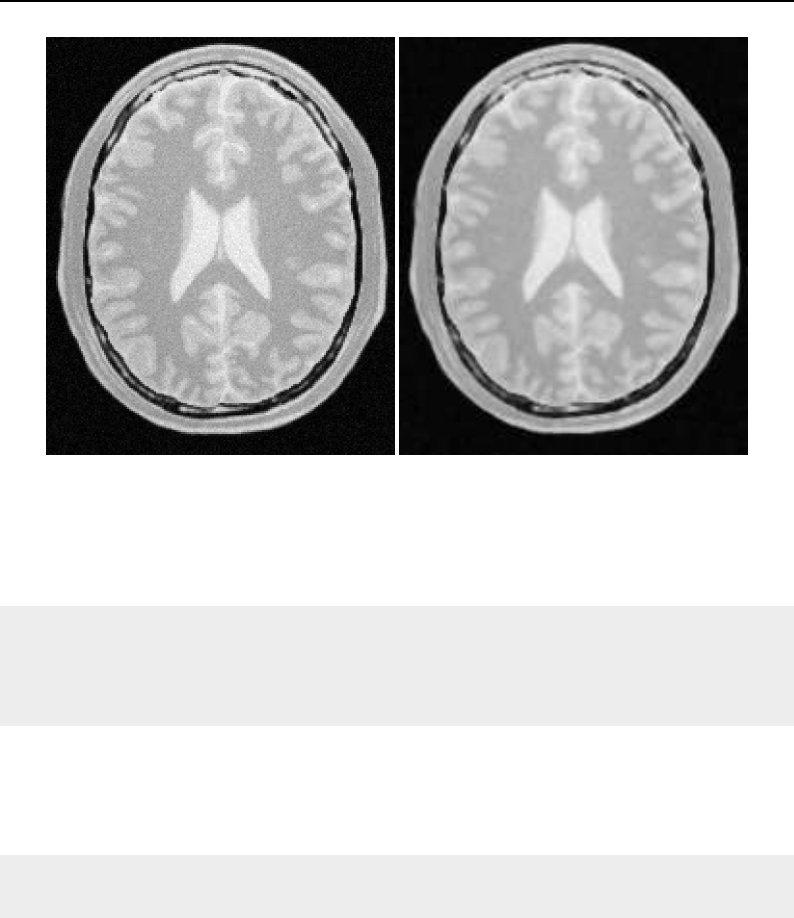

The National Library of Medicine Insight Segmentation and Registration Toolkit, shortened as the

Insight Toolkit (ITK), is an open-source software toolkit for performing registration and segmenta-

tion. Segmentation is the process of identifying and classifying data found in a digitally sampled

representation. Typically the sampled representation is an image acquired from such medical instru-

mentation as CT or MRI scanners. Registration is the task of aligning or developing correspondences

between data. For example, in the medical environment, a CT scan may be aligned with a MRI scan

in order to combine the information contained in both.